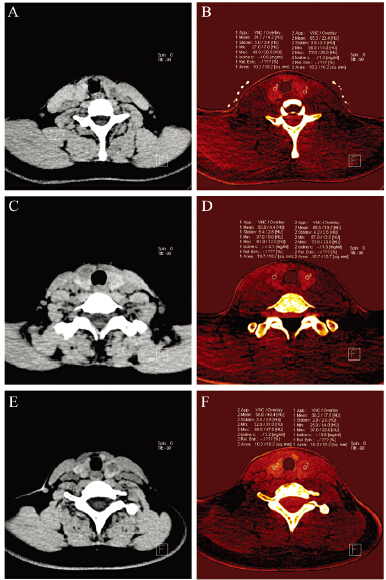

47个甲状腺结节中恶性结节20个(包括乳头状 癌17个、滤泡状癌2个、髓样癌1个),良性结节27 个(包括结节性甲状腺肿17个、甲状腺腺瘤10个)。 CT值及碘值范围的测定值,见表 1、图 1A~D。其中 各组CT值与碘值具有相关性(r=0.755、0.678、 0.813、0.774,P=0.000),见图 2。良性结节实性 部分的CT值及碘含量高于恶性结节,差异有统计 学意义(t=6.213,Z=-4.650,P=0.001,0.000 )。 而良性与恶性结节周围正常组织的CT值及碘含量 差异无统计学意义(t=3.753、0.932,P=0.225, 0.112)。

| A,B: Female,32 years old,left thyroid nodule(adenoma) border was clear,the density was not homogeneous. Iodine was 0.6mg/ml; C,D: Male,46 years old,right thyroid nodule(papillary carcinoma) border was not clear,the density was not homogeneous. Iodine was -0.1mg/ml; E,F: Female,30 years old,left thyroid nodule(papillary carcinoma) border was not clear,the density was not homogeneous. Iodine was 0.6mg/ml 图 1 患者甲状腺结节CT及碘值 Figure 1 The CT attenuation value and iodine concentration of thyroid nodules |

CT形态学诊断为恶性结节21个,良性结节26 个,其诊断敏感度为65.00%、特异性为70.37%。以 碘值等于0.15 mg/ml为诊断标准的诊断结果(结节 内碘值≤0.15 mg/ml为恶性,结节内碘值>0.15 mg/ ml为良性)与CT形态学诊断结果经Kappa检验,具 有较高一致性(Kappa值为0.742),其中均诊断为 良性的有23例,均诊断为恶性18例,3例碘值诊断 为良性结节,形态学诊断为恶性,3例碘值诊断为 恶性结节,形态学诊断为良性,见图 1E、1F。 3 讨论